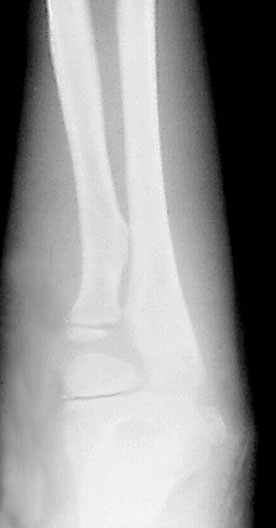

Elbow Growth Plates

1. Radial Growth Plate

2. Humeral Growth Plate